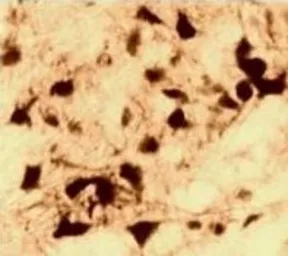

IHC-P analysis of primate brain tissue using GTX22742 Androgen Receptor antibody [AN1-15].